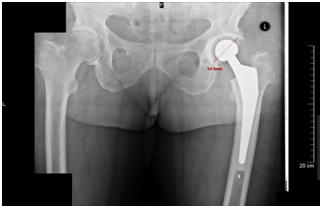

Three independent orthopedic surgeons were invited to participate as observers during this study. Each of them had to measure the biggest diameter of acetabular component in postoperative radiographs after primary THA twice at one-month interval (Figure 1). Observers were provided as much time as needed for accurate evaluation of x-ray photos. The measurements were made under MF of 0 %. The predictive MF of 15% is used by our institution during preoperative planning with the assumption that the distance between the x-ray emitter and film is 110 – 115 cm and a patient is as close to the x-ray film as possible. The actual size of acetabular component was taken from the local register of hip arthroplasty. True MF was calculated as the actual size of acetabular cup divided by the measured diameter of cup multiplied by 100. The accuracy of predictive MF was calculated as the predictive MF divided by the true MF multiplied by 100. 100% accuracy would indicate that the predictive MF and the true MF are equal, while lower value of accuracy indicates greater discrepancy between the true and predictive MF.

Figure 1 Measurement of the largest diameter of acetabular cup in postoperative radiograph after primary total hip arthroplasty.